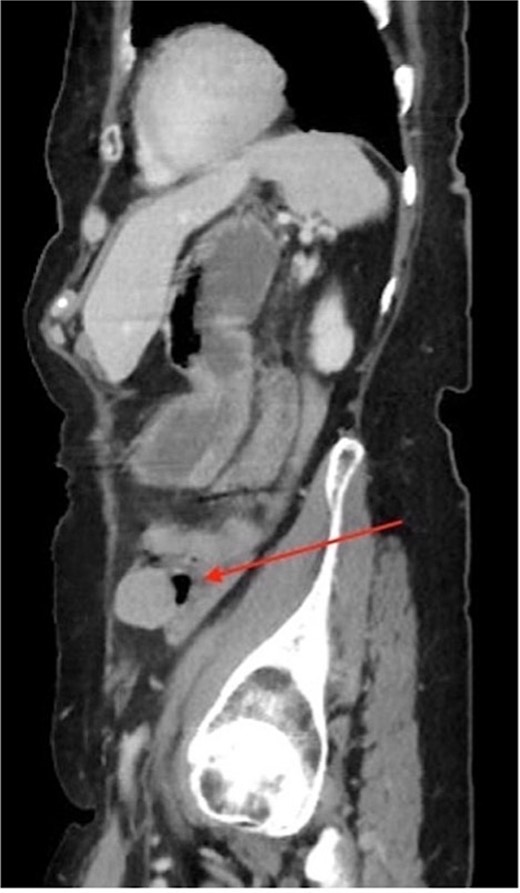

An 84-year-old female with an R0 oncologic hepatic resection for HCC 11 years ago presented with high alpha-fetoprotein (AFP) levels, followed by a computed tomography (CT) scan revealing a pelvic mass. After her index hepatic resection, she was managed with serial imaging and AFP tumor marker levels. The most recent AFP was elevated at 20.4 ng/ml, up from a previous value of 1.5 ng/ml one year earlier (normal range < 6.1 ng/ml). The CT demonstrated a 2.7 cm heterogeneous mass in the left lower quadrant, which was suspicious for a neoplasm. (Figs 1 and 2) The patient denied having abdominal symptoms, and the mass was not palpable during the physical exam.

CT imaging of the pelvis (sagittal section) displaying the left localization of the 2.7 × 2.7 cm heterogeneous pelvic mass.